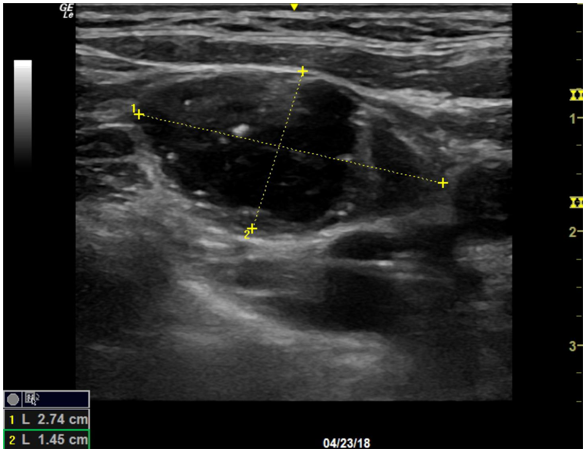

Figure 3: Ultrasound image of suspicious 2.7 cm left lateral neck lymph node, concerning for metastatic disease.

The patient was seen in follow-up after the isthmusectomy for further surgical planning which included a lateral neck ultrasound. This ultrasound showed suspicious lateral neck disease concerning for metastatic medullary thyroid cancer with multiple enlarged lymph nodes, the largest being a deep level IV lymph node measuring 2.74 cm. She had a normal serum calcitonin level (<1.0 pg/ml) and normal serum calcium (9.7 mg/dL). Plasma metanephrine was normal (0.13 nmol/L), and plasma normetanephrine was normal (0.38 nmol/L), ruling out pheochromocytoma. The tumor marker Chromogranin A was negative. An FNA biopsy of one of the suspicious lateral neck lymph nodes was performed at this same follow up visit.